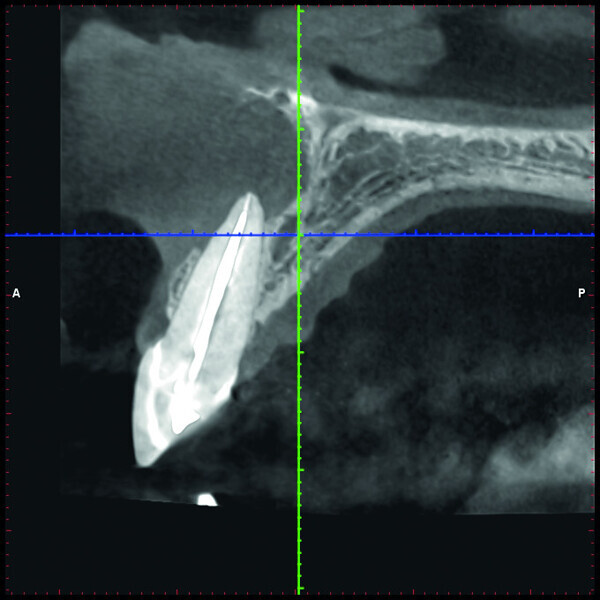

Fig. 2c: Conventional radiograph of an endodontically treated tooth #11 and cold-sensitive tooth #12 compared with CBCT imaging showing the presence of a large apical bone defect (taken at a two-day interval).